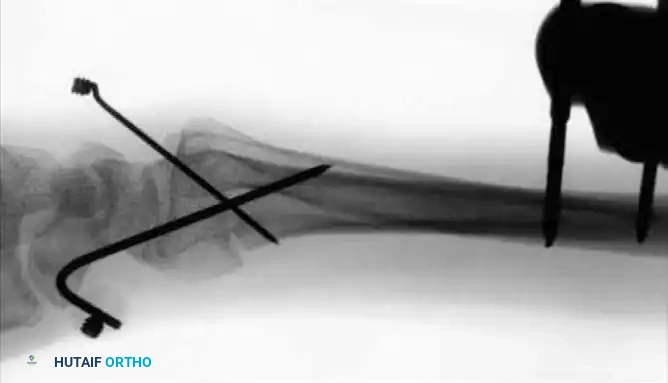

- Percutaneous Pinning: For unstable fractures without severely depressed central articular fragments, introduce 0.045-inch or 0.0625-inch K-wires into the fracture fragments. A crossed-pin configuration significantly increases torsional and bending stability.

- Drive one or two pins through the radial styloid fragment, and one through the dorsal ulnar fragment, directing them proximally into the intact radial shaft.

- Cortical Purchase: Pins should pierce the ulnar cortex of the proximal radius to achieve bicortical purchase, but must not penetrate across the interosseous space into the ulnar shaft, which would block forearm rotation.

- Cut the pins approximately 1 cm external to the skin margin and bend them at an acute angle to prevent migration.